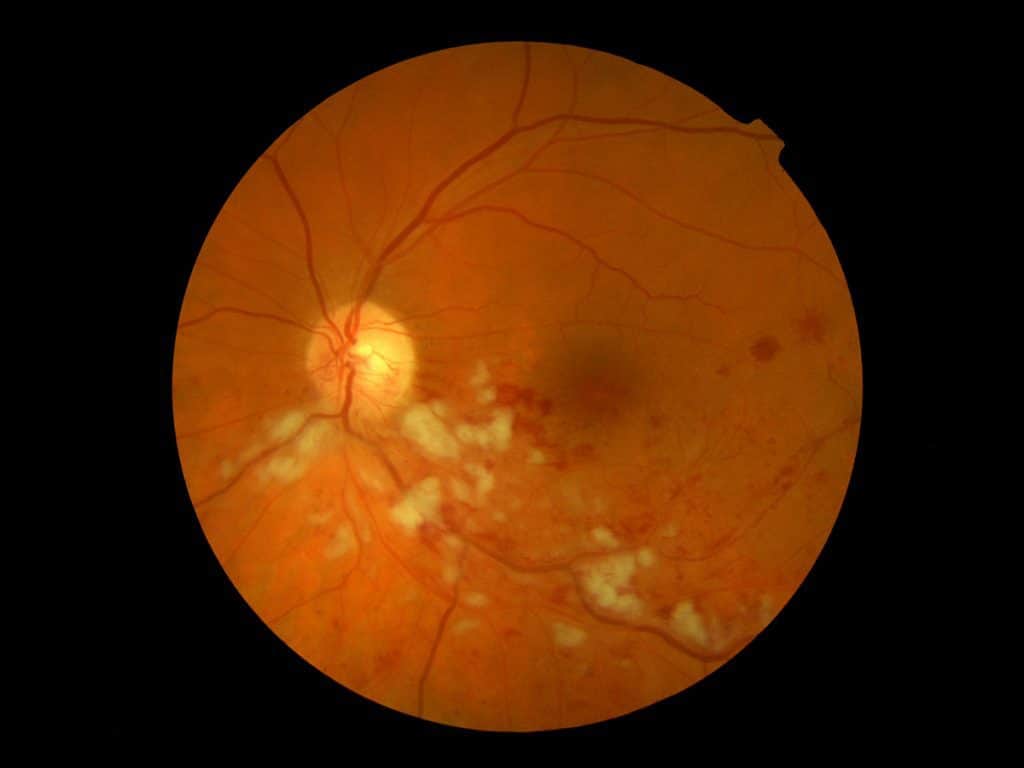

Es gibt verschiedene Erkrankungen der Netzhaut/Makula, die mit einer Schwellung der Netzhautmitte (=Makulaödem) einhergehen. Dies kann der Fall sein z.B. bei:

- altersbedingter Makuladegeneration (feuchte AMD)

- Diabetes

- Gefäßverschlüssen an der Netzhaut (Thrombosen)

- Gefäßneubildungen bei starker Kurzsichtigkeit (myope CNV)

- chronischer Entzündung der Aderhaut (Uveitis)

Diese Schwellung, die mithilfe eines modernen hochauflösenden OCT diagnostiziert werden kann, führt zu einer Verschlechterung der zentralen Sehschärfe. Durch die Eingabe eines entsprechenden Medikaments in das Augeninnere (intravitreale Injektion) kann diese Veränderung behandelt oder zumindest stabilisiert werden. Es können allerdings wiederholte Eingaben dieser Medikamente erforderlich werden.